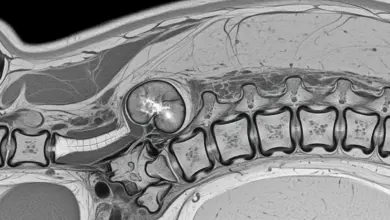

Espondilodiscite piogênica: o que é, sintomas e como tratar

Espondilodiscite piogênica é uma infecção que acomete o disco intervertebral e, com frequência, as vértebras vizinhas. O ponto central é…